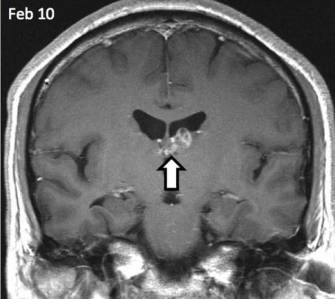

Ez az első alkalom a férfi megfordult, hogy az orvosok négy évvel ezelőtt, ő fejfájásra panaszkodott, és furcsa szagot. Az orvosok, akik végzett felmérés, megzavarodtak kóros területeket az agyban, hogy az MRI kimutatta. Megfigyelések a következő években azt mutatta, hogy a rendellenesség által mozgatott öt centiméter, írja a The Guardian.

Az orvosok a St. Thomas Kórház beteg HIV-tesztet, a szifilisz és a különböző fertőző betegségek. Ennek eredményeként, a biopszia jelenlétét mutatta galandféreg. Genetikai Wellcome Trust Sanger Institute Cambridge megállapítottuk, hogy ez egy rendkívül ritka parazita ismert Spirometra erinaceieuropaei.

Mivel az orvosok azt mondják, a beteg szokatlanul szerencsés a féreg okozhat az egészsége jelentősen több kárt. Például rakják le tojásaikat. Akkor ez lenne a lárvák a szövetekből az agyban.